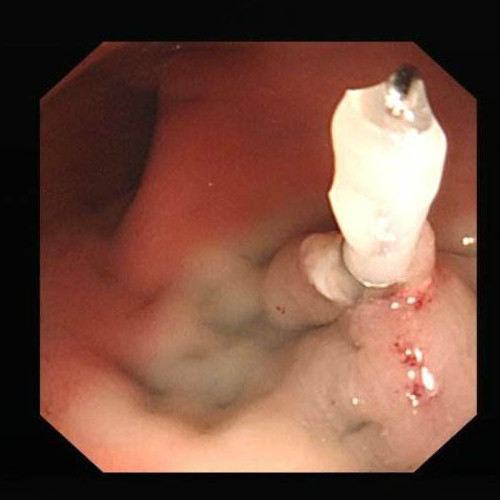

腸息肉圖片

息肉

息肉的